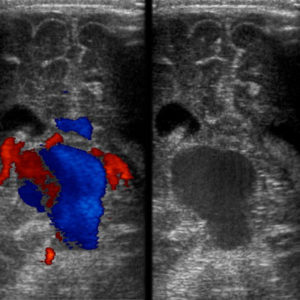

The diagnosis of VOGMs is typically postnatal, but it can be detected antenatally in approximately 29% of cases. On antenatal ultrasound, VOGMs are generally observed from 25 weeks of gestation and may appear as cystic midline brain lesions, as demonstrated in the ultrasound image, Figure 2. Color Doppler imaging can then reveal abnormal blood flow, a finding sometimes referred to as the ‘comet tail’ sign, as shown in Figure 3. Antenatal magnetic resonance imaging (MRI) can also be used to confirm the diagnosis. It allows evaluation of any brain injury and helps with planning delivery in a facility with the necessary resources and expertise [7].

Figure 2. Transcranial ultrasound of the brain. Left: Doppler examination demonstrating abnormal flow within the vein of Galen with aneurysmal dilation. Right: Grey-scale image at the same level showing the aneurysmal dilation of the VOG [8].